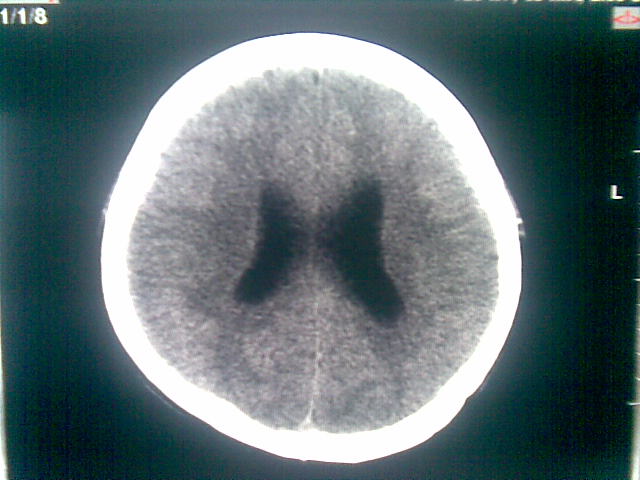

以下是引用随光逐影在2010-1-5 16:32:00的发言:[br]1)鞍上池囊性占位性病变,不排除蛛网膜囊肿可能;建议行mri检查。2)脑积水。

以下是引用yangyang2000在2010-1-5 20:41:00的发言:[br])鞍上池囊性占位性病变,不排除蛛网膜囊肿可能;建议行mri检查。2)脑积水

以下是引用yangyudong333在2010-1-5 21:28:00的发言:[br]1)鞍上池囊性占位性病变,不排除蛛网膜囊肿可能;建议行mri检查。2)脑积水。